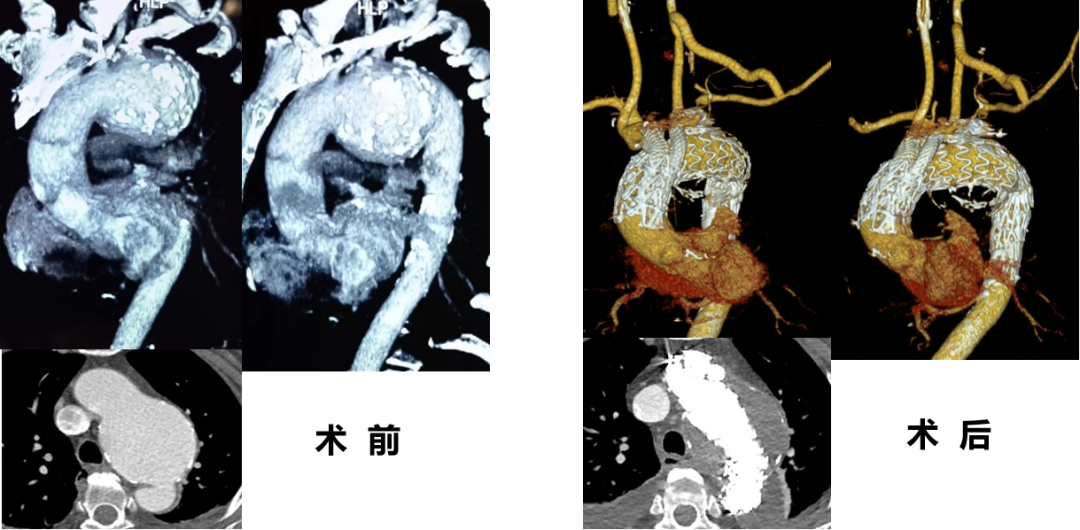

★ 病例2:模块内嵌分支胸主动脉覆膜支架系统

术前

术后